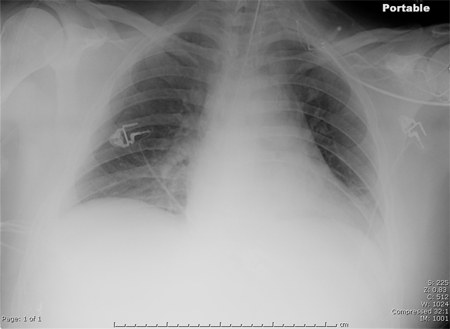

Portable chest x-ray of a patient with HAP. Note obscured left hemidiaphragm due to a left lower lobe opacity and an obscured heart border due to a left upper lobe or lingular opacity

Consent obtained at University of Louisville, KY